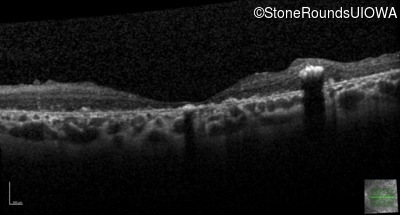

Optical Coherence Tomography - Right - 20/400 sc

Exemplar / OCT Stack